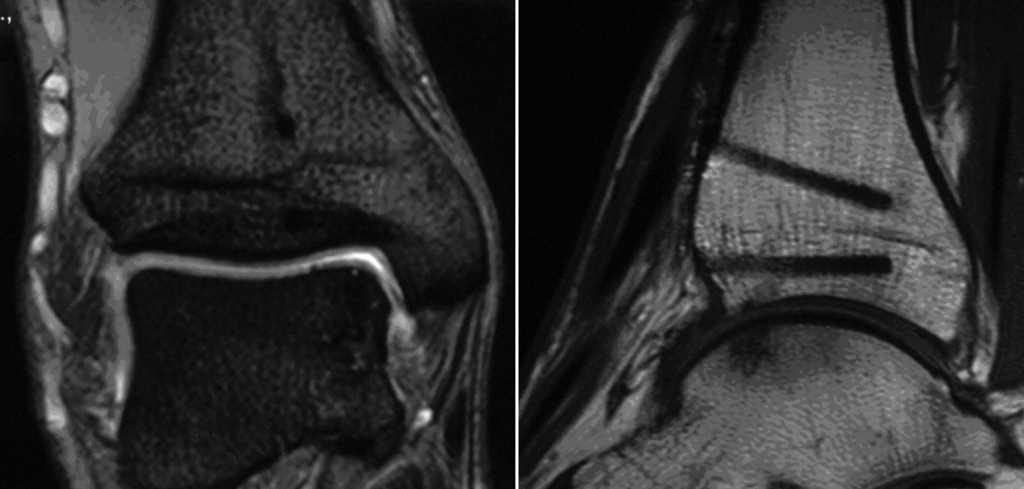

* Control radiológico a las 6 semanas en dos planos (fig. 14). Si el injerto se ha integrado correctamente, se incrementa progresivamente la carga hasta alcanzar la carga completa en torno a las 12 semanas.

Figuras 14a y b

Radiografías del tobillo en dos planos, a las 6 semanas de la intervención. Las cabezas de los implantes están recubiertas de fábrica con un marcador radioopaco, se identifican en la imagen como puntos. El bloque de hueso ha consolidado sin escalones y apenas se diferencia del hueso circundante. El cilindro está en una posición perfecta pero no se ha integrado completamente.